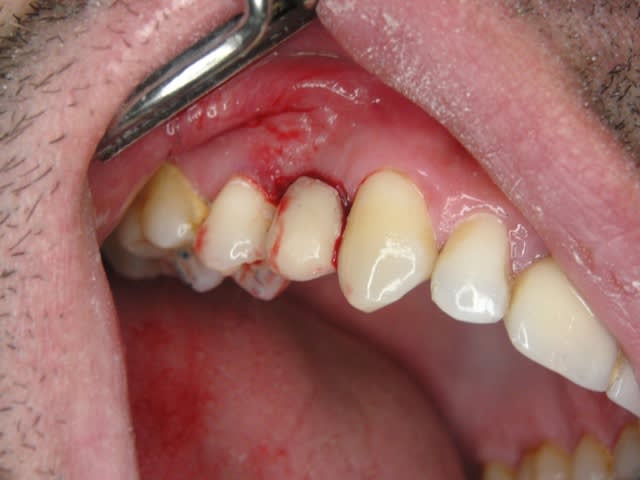

Un patient de 52 ans présente une fracture de racine au site 26.Après division de la racine, extraction de la dent,préparation de la cavité avec un foret conique triangulaire (3 faces,condensation de l´os), puis implantation à 50 Ncm (implant 10mm long, 4,5mm diamètre).Utilisation d´acide hyaluronique pour stimuler la synthèse des ostéoblastes.Pose d´un clip gingival pour préformer la gencive.Après 7 semaines, réalisation d´une empreinte fermée en 5 minutes.Une semaine après, fixation de la couronne définitive ( on observe déjà une ostéointégration).

Pour l acide hyaluronique il existe des études americaines et allemandes par exemple celle de l université de Leipzig , Professeur Dr Holger Jentsch qui montre la stimulation des osteoblastes et fibroblastes.De façon personnelle je l utilise depuis 3 ans et ça fonctionne réellement.

Ce qui m'intéresse plus dans ce cas c'est la gestion des tissus mous autour de la bague en post-op : si la chirurgie en mini-invasive, comment tracter les tissus mous en peri-implantaire, la bague me semblant bien étroite pour "remplir" le volume entre le (petit) diamètre de l'implant et le (grand) volume de l'extraction ?

Comblement en plus de l'ac Hyalur, membrane, et quelles sutures ?